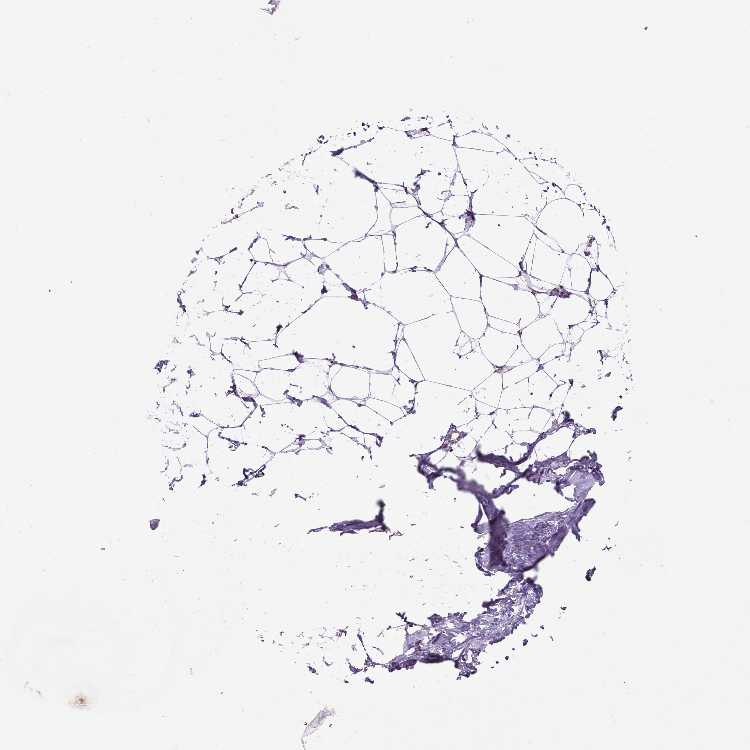

BREAST - Antibody stainingi

Antibody staining in the annotated cell types in the current human tissue is reported as not detected, low, medium, or high, based on conventional immunohistochemistry profiling in selected tissues. This score is based on the combination of the staining intensity and fraction of stained cells.

Each image is clickable and will lead to virtual microscopy that enables deeper exploration of all samples and also displays staining intensity scores, fraction scores and subcellular localization as well as patient and tissue information for each sample.

Antibody HPA069538

Adipocytes Not detected

Glandular cells Medium

Myoepithelial cells Low